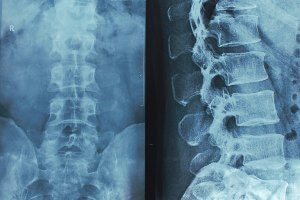

spinal cord x-rayMany severe spinal cord injuries are caused by blunt force trauma, such as from a car crash or fall, but some may occur during medical treatment. For instance, doctors could misdiagnose an injury or make a surgical error. Sometimes these issues may rise to the level of medical malpractice.